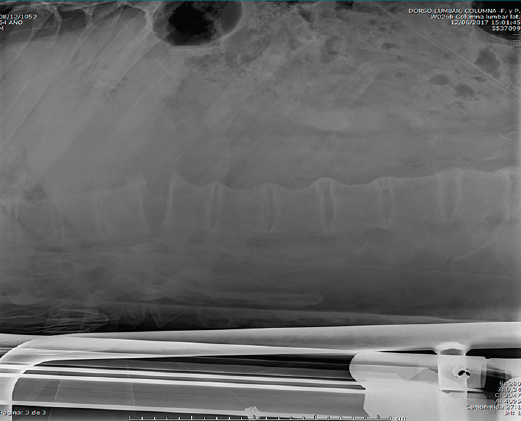

Después de realizar un control radiológico postoperatorio (Figura 6), inició la deambulación con ortesis semirrígida dorsolumbar en el postoperatorio inmediato. Mantuvimos la ortesis durante 2 meses, iniciando la rehabilitación con una evolución clínica excelente.

Figura 7. Control a los 2 meses de la cirugía.

Se realizó un control a los 2 meses de la cirugía, previo al inicio de rehabilitación (Figura 7).